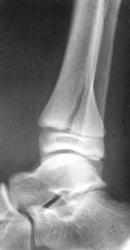

Перелом-эпифизеолиз дистального метаэпифиза ББК со смещением под углом кзади, перелом н/3 диафиза МБК

А щель перелома разве не уходит в диафиз?

Да, линия перелома распространяется и на диафиз